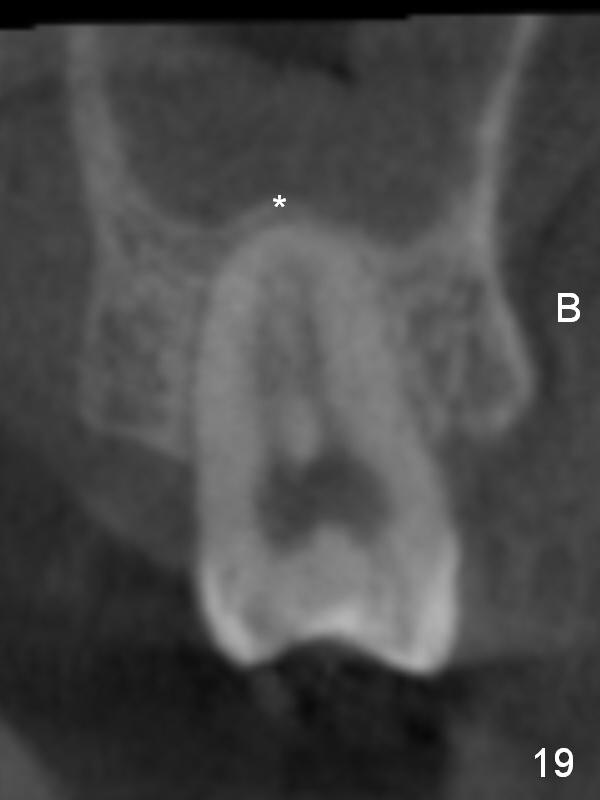

CBCT taken 23 months post cementation shows no abnormality (Fig.15-17). On the contralateral side, the apex of the tooth #15 is immediately inferior to the sinus floor (Fig.18 (sagittal section), 19 (coronal section)). The immediate implant seems to be unavoidably entering the sinus. The implant seems to be normal 3 year 5 months post cementation.